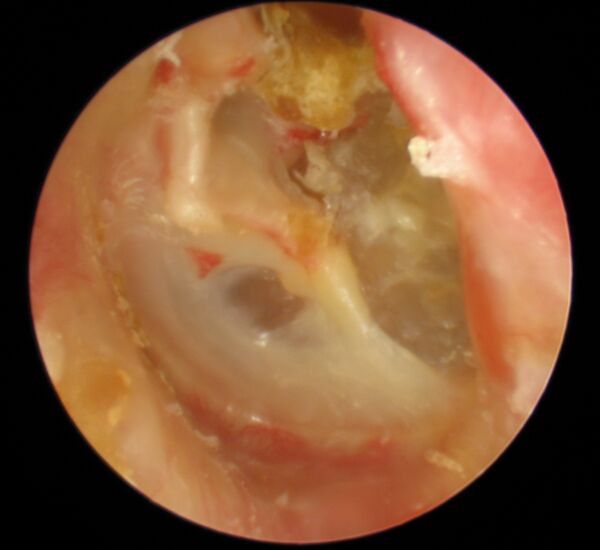

Предварительный диагноз устанавливается путём отоскопии. Характерными признаками являются краевая перфорация (прободение) барабанной перепонки, наличие творожистых масс беловато-серого цвета. Можно наблюдать частицы холестеатомы в промывных водах из барабанной полости. Для подтверждения диагноза производят компьютерную томографию.